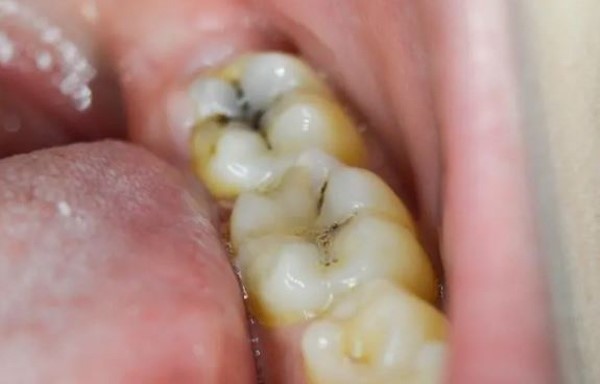

• Sâu răng là một trong những vấn đề phổ biến ở hầu hết mọi người, đặc biệt là ở trẻ em và người già. Nếu không được điều trị kịp thời, nó có thể gây ra các vấn đề nghiêm trọng như viêm lợi, viêm nướu hoặc thậm chí là mất răng. Vì vậy, việc bảo vệ và chữa trị sâu răng là rất quan trọng để duy trì sức khỏe răng miệng. Cây lá lấu là một loại thực phẩm tự nhiên với nhiều tác dụng hữu ích cho sức khỏe, trong đó có khả năng chữa trị sâu răng. Trong bài viết này, Nha khoa Asia sẽ giải thích chi tiết cách dùng cây lá lấu chữa sâu răng hiệu quả tại nhà.